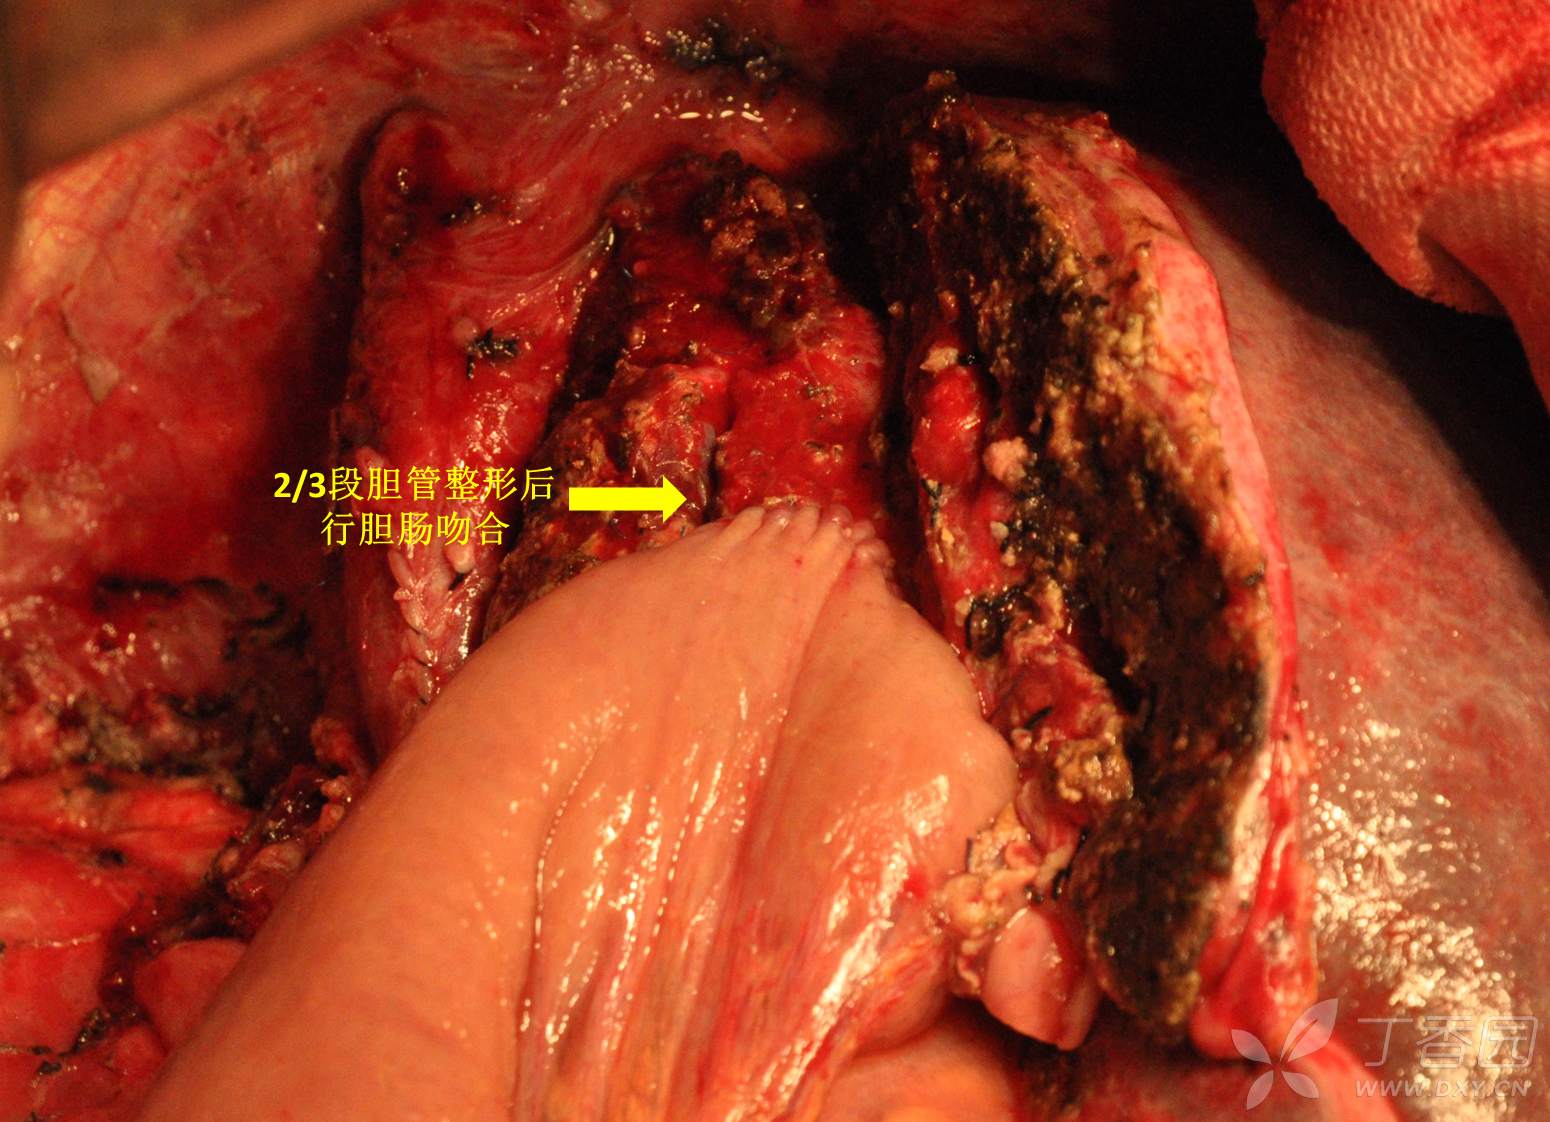

然后就前入路一直劈下去,注意保护好左肝静脉汇入下腔处。下腔静脉最后用心耳钳夹闭后离断,完整移除标本后将下腔静脉连续缝合关闭。2/3段胆管汇合部劈开少许并整形后行胆肠吻合。主要操作完毕。